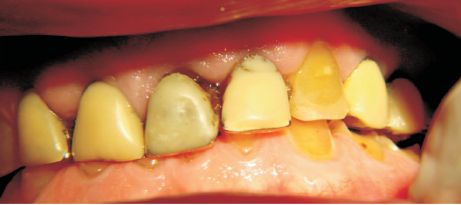

CASOS CLÍNICOS.-

Fig.5

Fig.6

Figs. 5 y 6. Paciente 28 años, sexo masculino, desgaste erosivo típico con estrías en el esmalte, fracturas de bordes incisales, seudo chamfer en palatino y difuminado de la anatomía dentaria. Alto consumo de frutas y jugos cítricos afectaron gravemente el sector antero superior. Erosión por dieta ácida con atricción sobreagregada.